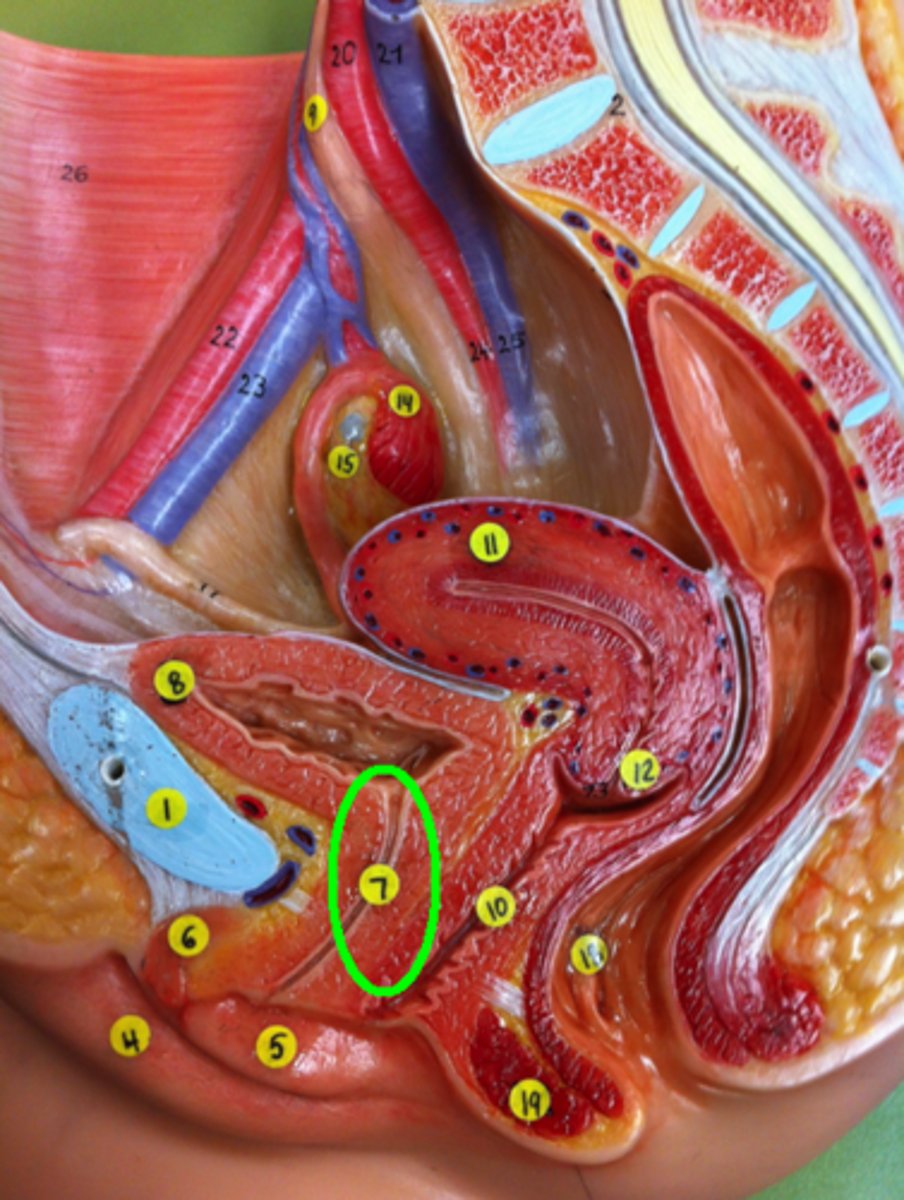

Urethra

Vagina

Uterus

Cervix of Uterus

Fimbriae of Uterine Tube

Ovary

Rectum

External Anal Sphincter